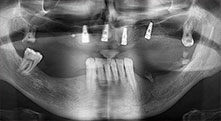

Could you describe briefly, for example, your procedure for mobilizing bone blocks for transplantation?

Bratu: We prefer to harvest bone from the external oblique ridge of the posterior mandible, not from the interforaminal region. After the soft-tissue incision, we use the new saws to define the amount of bone to harvest. With this approach, we also use them for the entire preparation in almost 80% of cases. We may also use other piezo instruments and then at the end a chisel to mobilize the block. We find that this is a very effective surgical technique.

Bratu: I consider piezo surgery a great leap forward in oral surgery. The technique makes bone preparation safer and easier. Little bone is lost, for example in extractions. This is very important in the aesthetic zone, particularly if immediate implantation is planned. Piezo surgery is also safer for soft tissue: injuries to membranes in the sinus are basically history, as are nerve injuries when bone blocks are being harvested. Data indicating reduced postoperative swelling and pain are also available. Piezo surgery is also ideal for preparation of sinus septa. And last but not least, our patients benefit from the atraumatic nature of this technology.